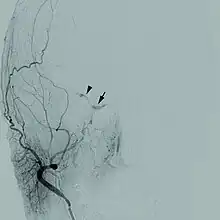

| Cerebral angiogram of a carotid-cavernous fistula | |